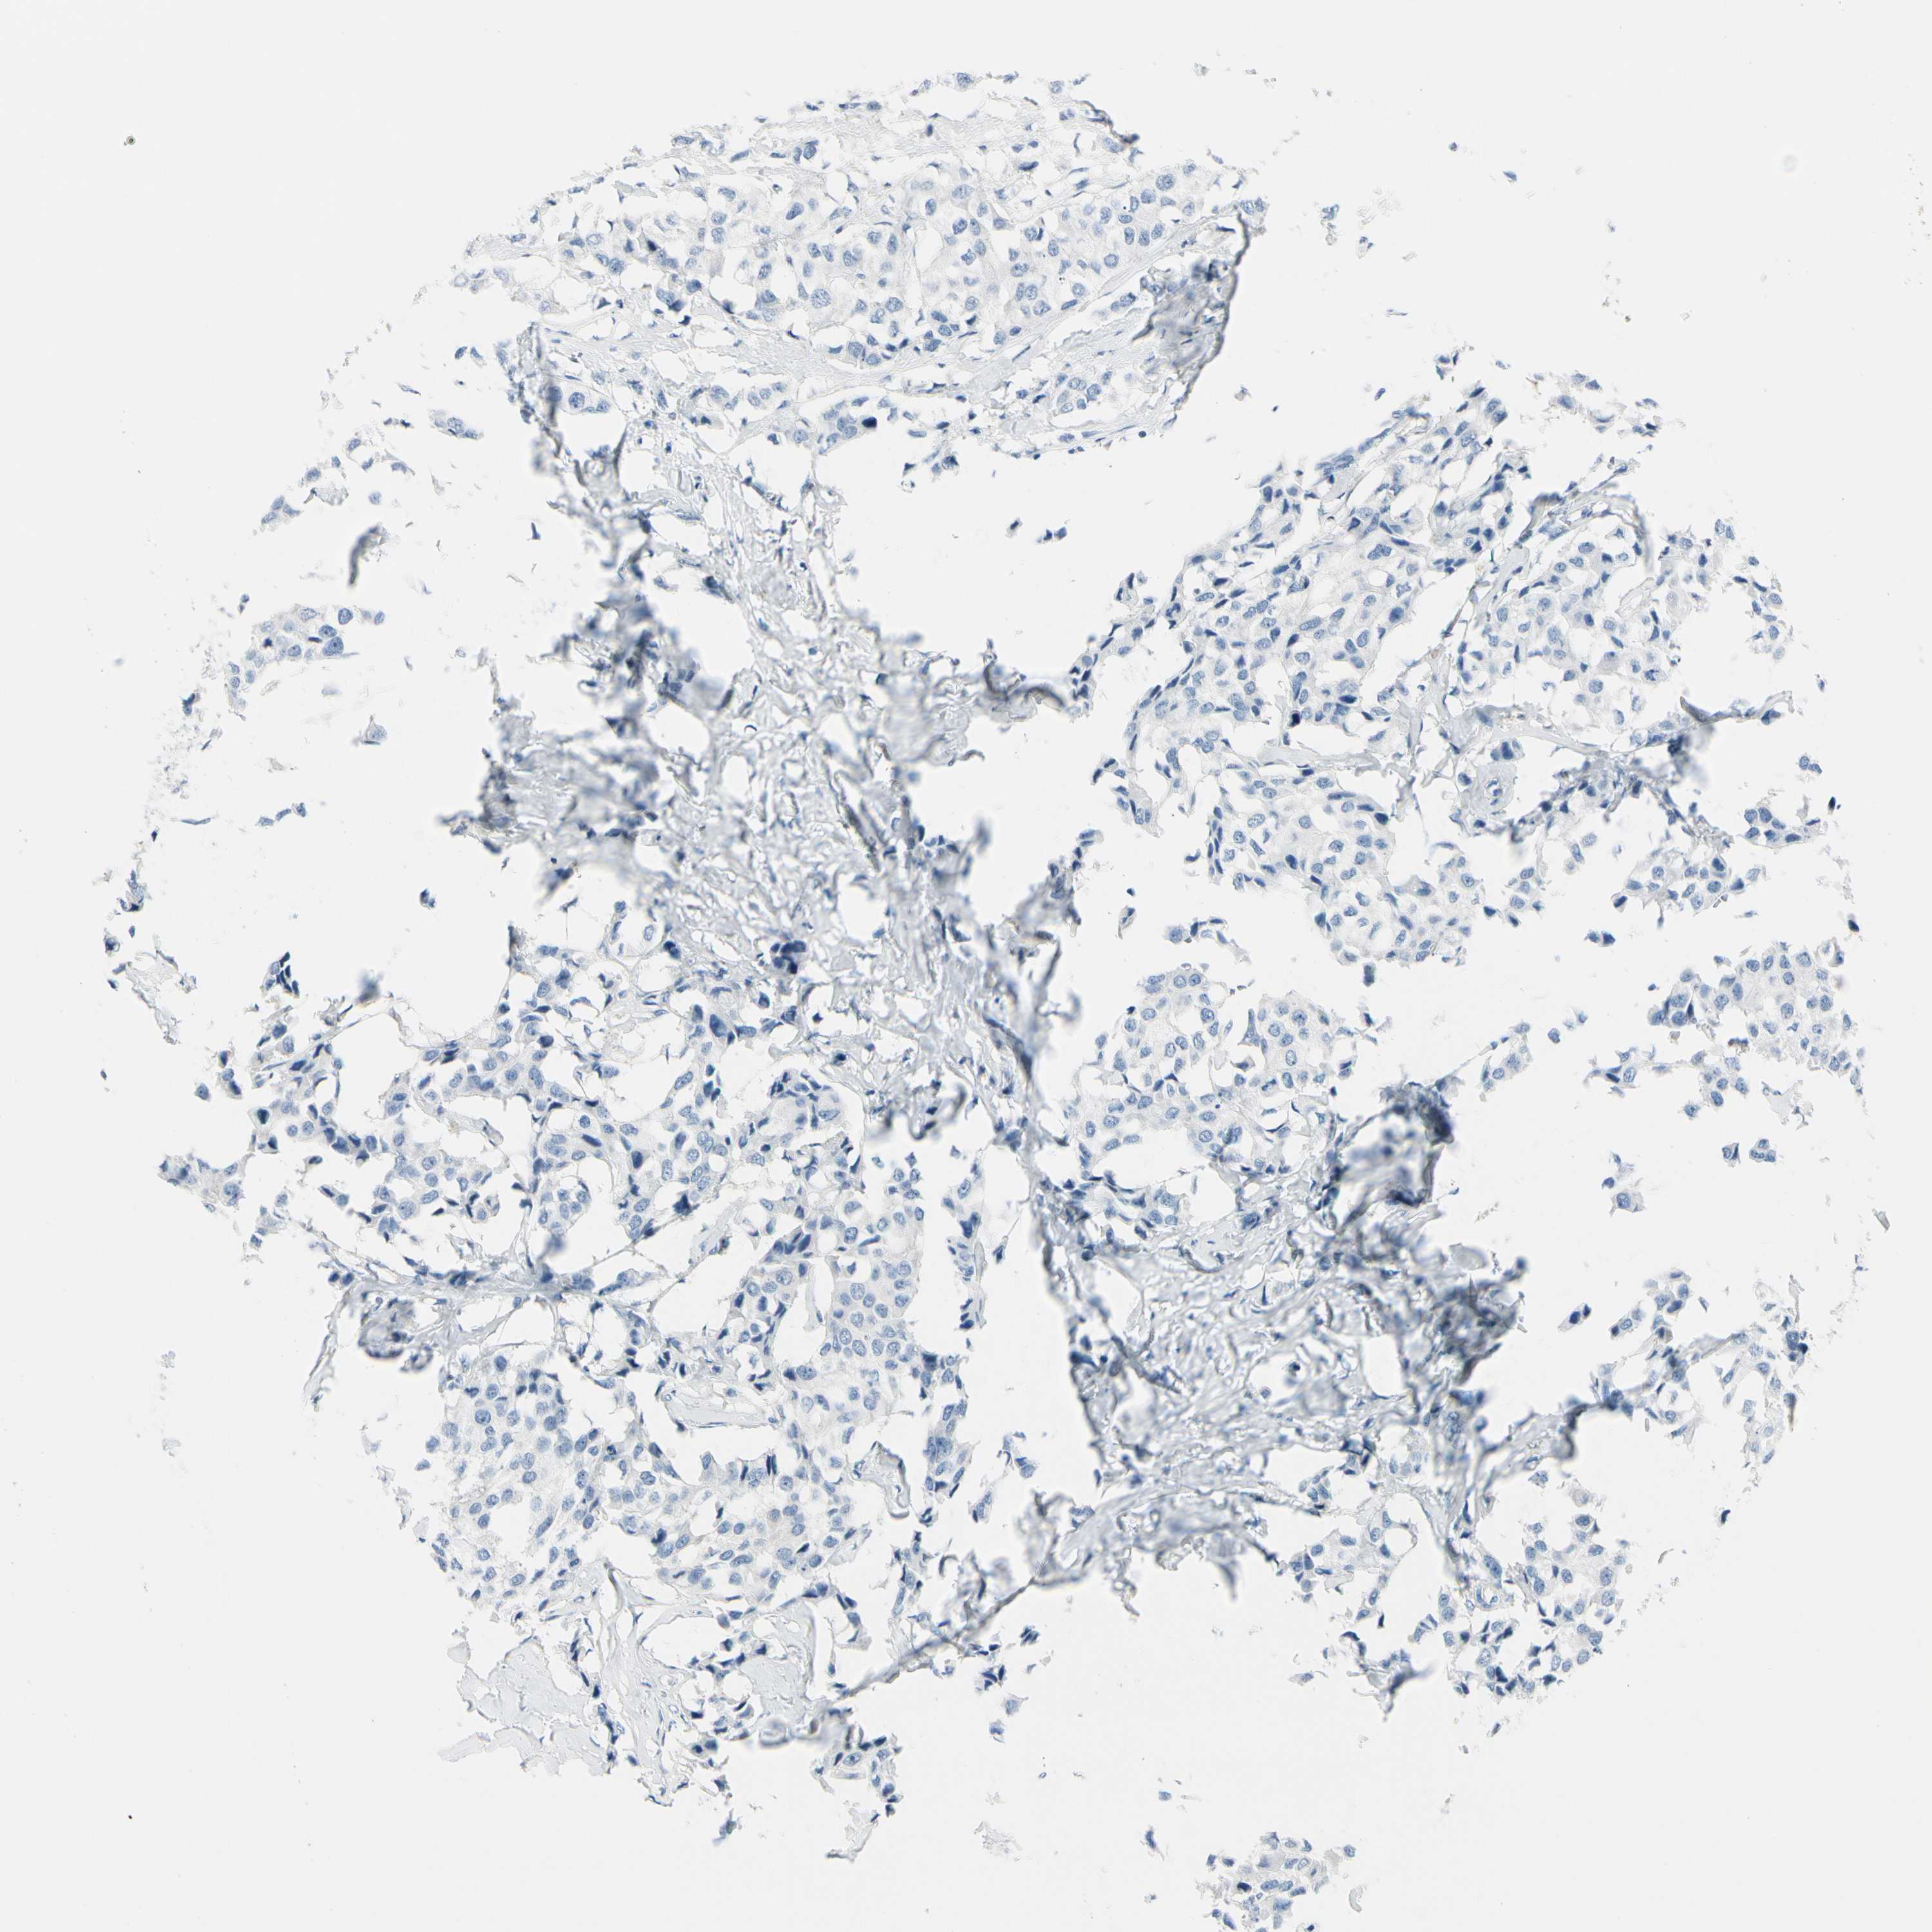

CANCER BREAST CANCER Show tissue menu

BRCA TCGA BRCA VALIDATION PROTEIN EXPRESSION

ANTIBODIES

AND

VALIDATION